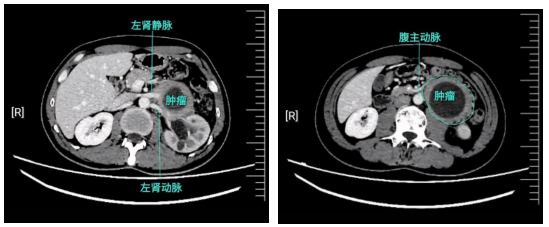

中新网黑龙江新闻1月5日电(刘璐)数月前,正值壮年的王先生(化名)被难以名状的腹胀所困扰。起初他并未在意,直到症状持续加重,影像检查结果提示:腹膜后巨大占位。

腹膜后间隙,是人体腹部最深在、最隐秘的“禁区”。前有腹腔脏器遮挡,后有脊柱与腰背肌肉保护,区域内密布腹主动脉、下腔静脉、肾脏、输尿管、胰腺、十二指肠及重要神经丛。该部位空间狭小、结构复杂,肿瘤往往“沉默”生长,直至体积巨大、侵犯关键结构时才会显现症状。

术中探查发现,情况比影像预估更为棘手:肿瘤质地坚韧,如藤蔓般紧密缠绕左肾动静脉,更像一块巨岩嵌顿于腹主动脉与脊柱之间,将左肾动静脉完全包裹,十二指肠也受推挤、明显变形。

手术面临三重巨大挑战:肿瘤与左肾动静脉关系“血肉模糊”,血管壁已受侵犯,切除过程犹如在心脏的“分支水管”上进行精细剥离与重建,随时可能引发致命性大出血;肿瘤实体紧密压迫腹主动脉——这条人体血液输送的“主干道”,稍有不慎便可能导致血管破裂;受挤压移位的十二指肠若在分离过程中受损,术后发生肠瘘将带来灾难性后果。